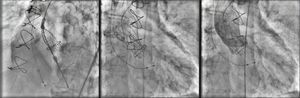

The patient was referred for aortic valve replacement surgery, but was refused on medical and surgical evaluation due to the high surgical risk (logistic EuroSCORE 22.3%). Percutaneous treatment was then considered, and anatomical assessment by transesophageal echocardiography and multidetector computed tomography showed this to be technically feasible. In particular, there was no significant iliofemoral arterial disease that would hinder access (Figure 2).